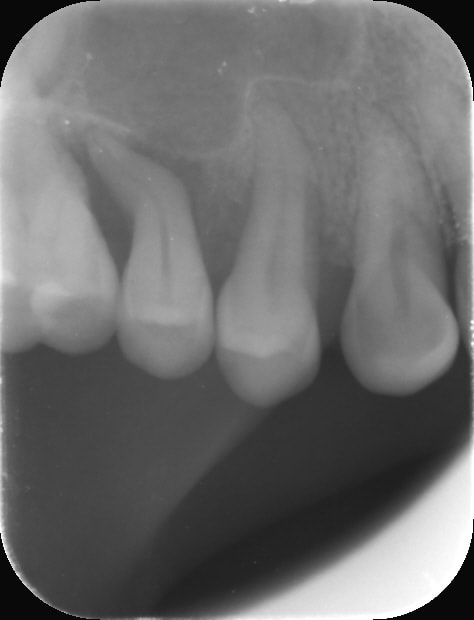

La meilleure obturation c'est la pulpe quand il n'y a pas de problèmes d'occlusion :

la dent bouge tellement qu'il y a du avoir en plus du traumatisme une section de la vascularisation apicale